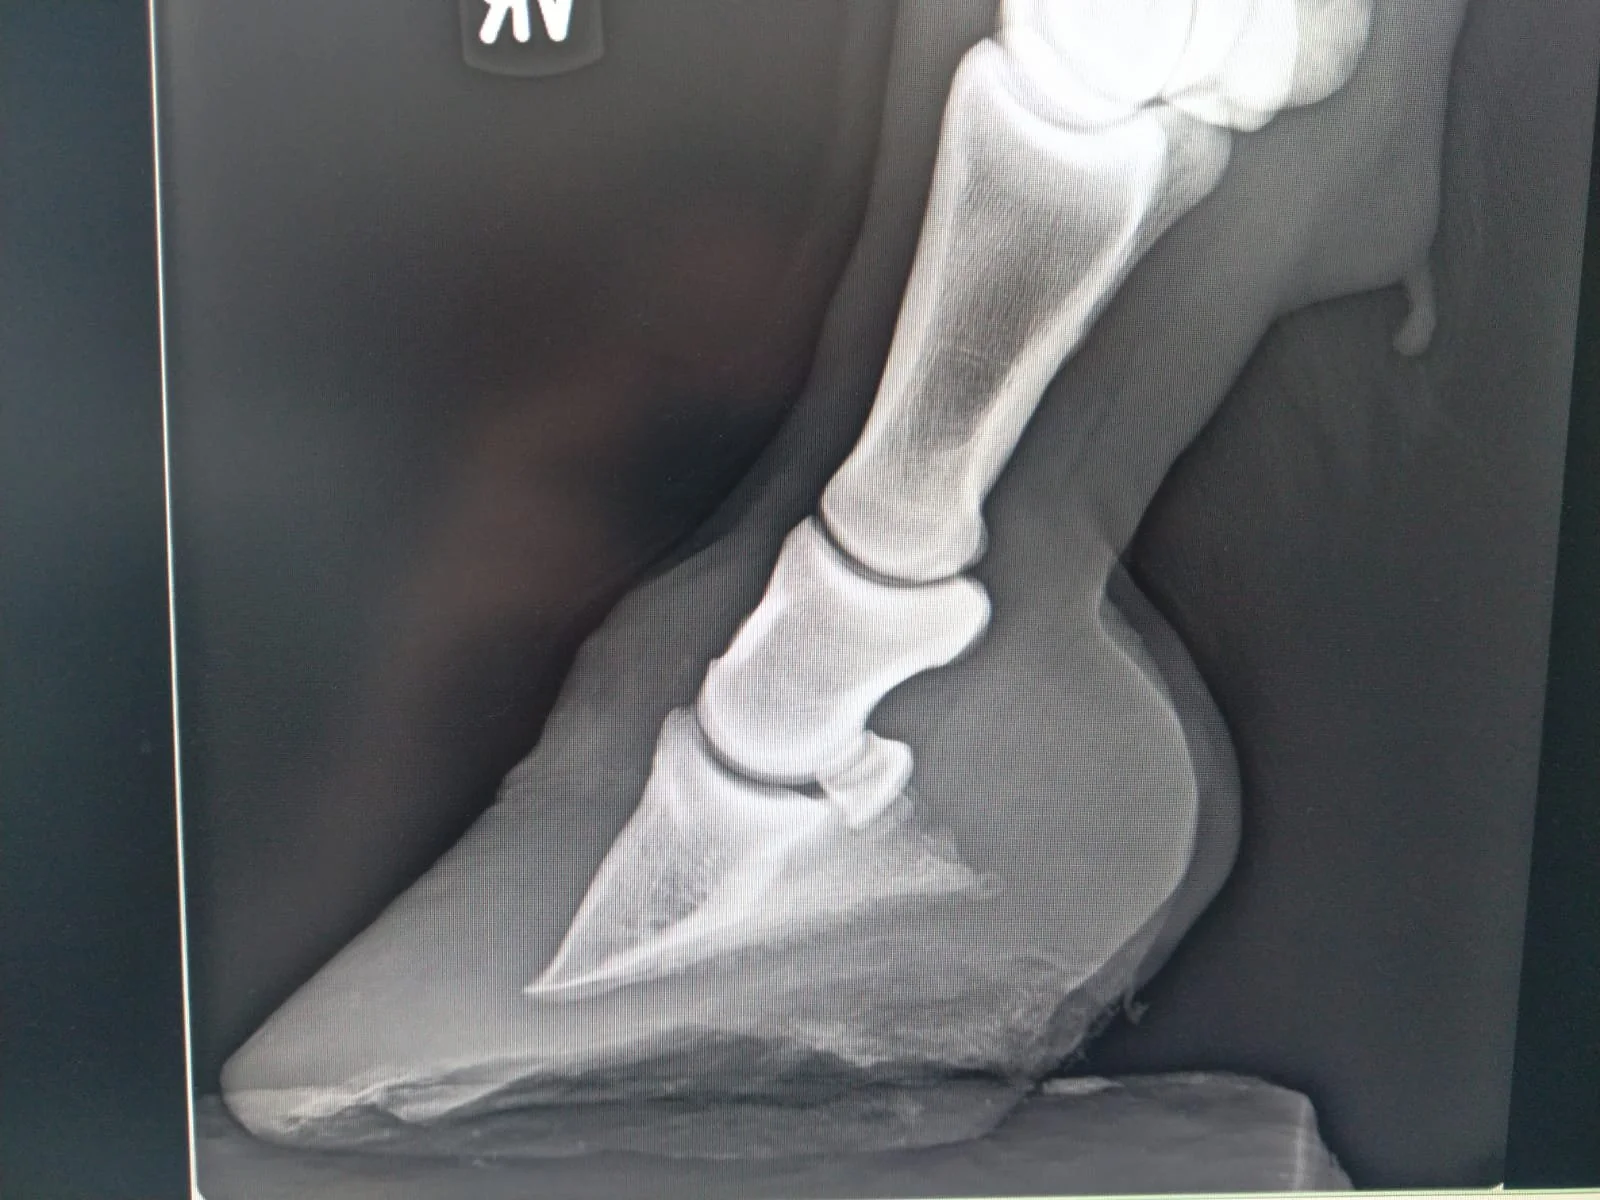

• Die Hufbeinrotation kann von einer Kapselrotation unterschieden werden. Die Hufbeinrotation bezeichnet die Rotation des Hufbeins um die Huf-Fessel-Achse. Die Spitze des Hufbeins kippt dabei nach unten, die Hufbein-Fessel-Achse wird nach vorne gebrochen und die Sohle und Sohlenlederhaut erfahren im Bereich der Hufbeinspitze starken Druck. Bei der Kapselrotation rotiert die Hufkapsel vom Hufbein weg. Die Hufbein-Fessel-Achse bleibt dabei unverändert. Dieses Wegrotieren kann durch eine Hufrehe, aber auch in geringerem Umfang durch eine zu lange Zehe entstehen. In beiden Fällen kann eine Hufrehe ursächlich sein und beide Fälle entstehen in Folge eines zerstörten Hufbeinträgers und somit in Folge eines nicht funktionalen Aufhängeapparats des Hufbeins.

• Bei einer Hufbeinsenkung sinkt das Hufbein innerhalb der Hornkapsel in Richtung Sohle ab. Auch hier ist das mechanische Versagen des Hufbeinträgers in Folge einer Hufrehe ursächlich. Röntgenologisch wird hierbei der Abstand zwischen Kronrand und der Oberkante des Hufbeins betrachtet. Ist der Abstand vergrößert, spricht man von einer Hufbeinsenkung.